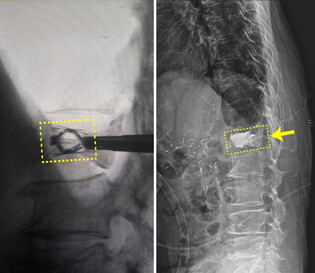

힘찬병원, 척추 압박골절 치료에 임플란트 이용한 보강술 시행

[mdtoday=김미경 기자] 목동힘찬병원과 (의)상원의료재단 인천힘찬종합병원이 척추 압박골절 치료에 임플란트를 이용한 경피적 척추 압박골절 보강술을 도입, 본격 시행에 들어간 가운데, 인천힘찬종합병원 척추센터에서 지난 25일 척추 ...